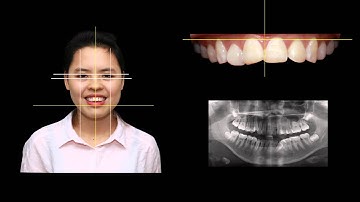

THIẾT KẾ RĂNG SỨ CÔNG NGHỆ CAD/CAM